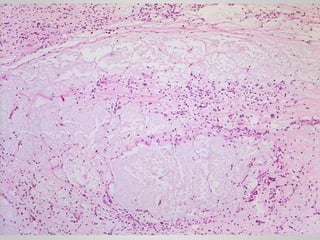

• Myxoid liposarcoma

• Abundant basophilic extracellular matrix, arborizing

capillaries and primitive cells at various stages of adipocyte

differentiation

• #17 Myxoid liposarcoma